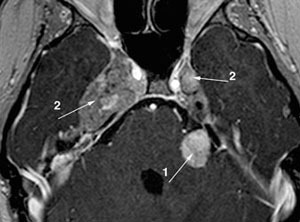

前庭神经鞘瘤(VS)是神经纤维瘤病2 (NF2)的标志,发生在95%的患者中。在前庭耳蜗神经上发展,并由于听力损失、耳鸣、失衡和脑干压迫的早期死亡风险而引起的发病率。NF2患者的听力随着时间的推移而下降,并且这些下降与逐渐增长有关。面部无力是面部神经鞘瘤切除手术的常见后遗症,也可能是继发于面部神经鞘瘤的较大面部神经鞘瘤的晚期表现,或作为孤立的单神经病变。面部无力会导致发音困难、口腔功能不全、缺乏微笑和表达情感的能力、无法眨眼和保护角膜,这些都会导致视力丧失。颜面无力和听力损失对生活质量有负面影响,因此在临床试验中代表了重要的功能结果。

NF2的处理首先要及早,虽然出生时就有基因突变,但我们的研究发现,在病变部位发生二次基因突变(肿瘤发生机制会在后面讲到)直到肿瘤长到可以被识别需要平均十年左右。对于多数病人来说,如果早期就诊,肿瘤没有危及生命的话,都可以得到正确的处理,半数以上病人可以长期有尊严的存活。一般其他部位肿瘤,小的话可以不处理,增大的话可以早期手术而不留严重后遗症。双侧听神经瘤既是NF2较主要的临床表现,又是NF2治疗的主要考量点,因为肿瘤本身或者手术放疗都会导致听力丧失,基于听力保存与重建的治疗策略是NF2治疗的基石和重要。